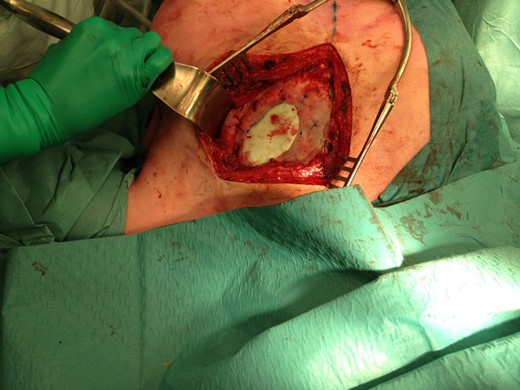

The size of the thoracic wall defect following resection measured 8 by 5.5 cm A patch was prepared using two polypropylene meshes and interpolate of methyl methacrylate (Fig. 3). The patch was placed and tightened to the periosteum using prolene sutures (Fig. 4). Figure 5 shows the resected tumour. Finally, subcutaneous tissue and skin were closed in layers using a Vicryl and intracutaneous Monocryl suture.

Preparation of the patch with two polypropylene meshes and interpolate of methyl methacrylate.

Positioning of the mesh and fixation to the periosteum of adjacent ribs.